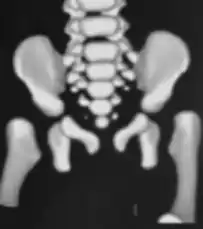

CT hips -

X-ray- dislocation of hips